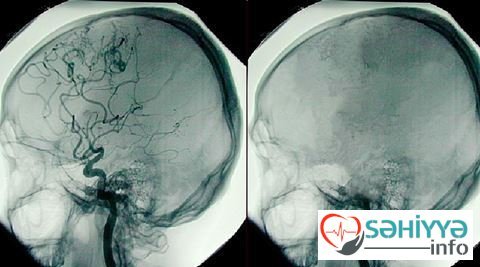

Çin vətəndaşının beynindən 13 santimetr uzunluğunda qurd çıxarılıb.

Sehiyye.info “ria.ru”ya istinadla xəbər verir ki, 23 yaşındakı gənc, 6 yaşından bəri ayaqlarında baş verən uyuşmadan əziyyət çəkdiyini bildirib. O, bədənin sağ yuxarı hissəsində hissiyatı tamamilə itidikdən sonra həkimə müraciət edib. Əməliyyat zamanı gəncin beynindən 13 santimetr uzunluğunda qurd çıxarılıb. Parazitin 13 ildir beyində yaşadığı məlum olub. Həkimlər parazitin beyinə qurbağa, ilan və sair bənzəri qidalardan düşə biləcəyini söyləyib.//Yeniavaz